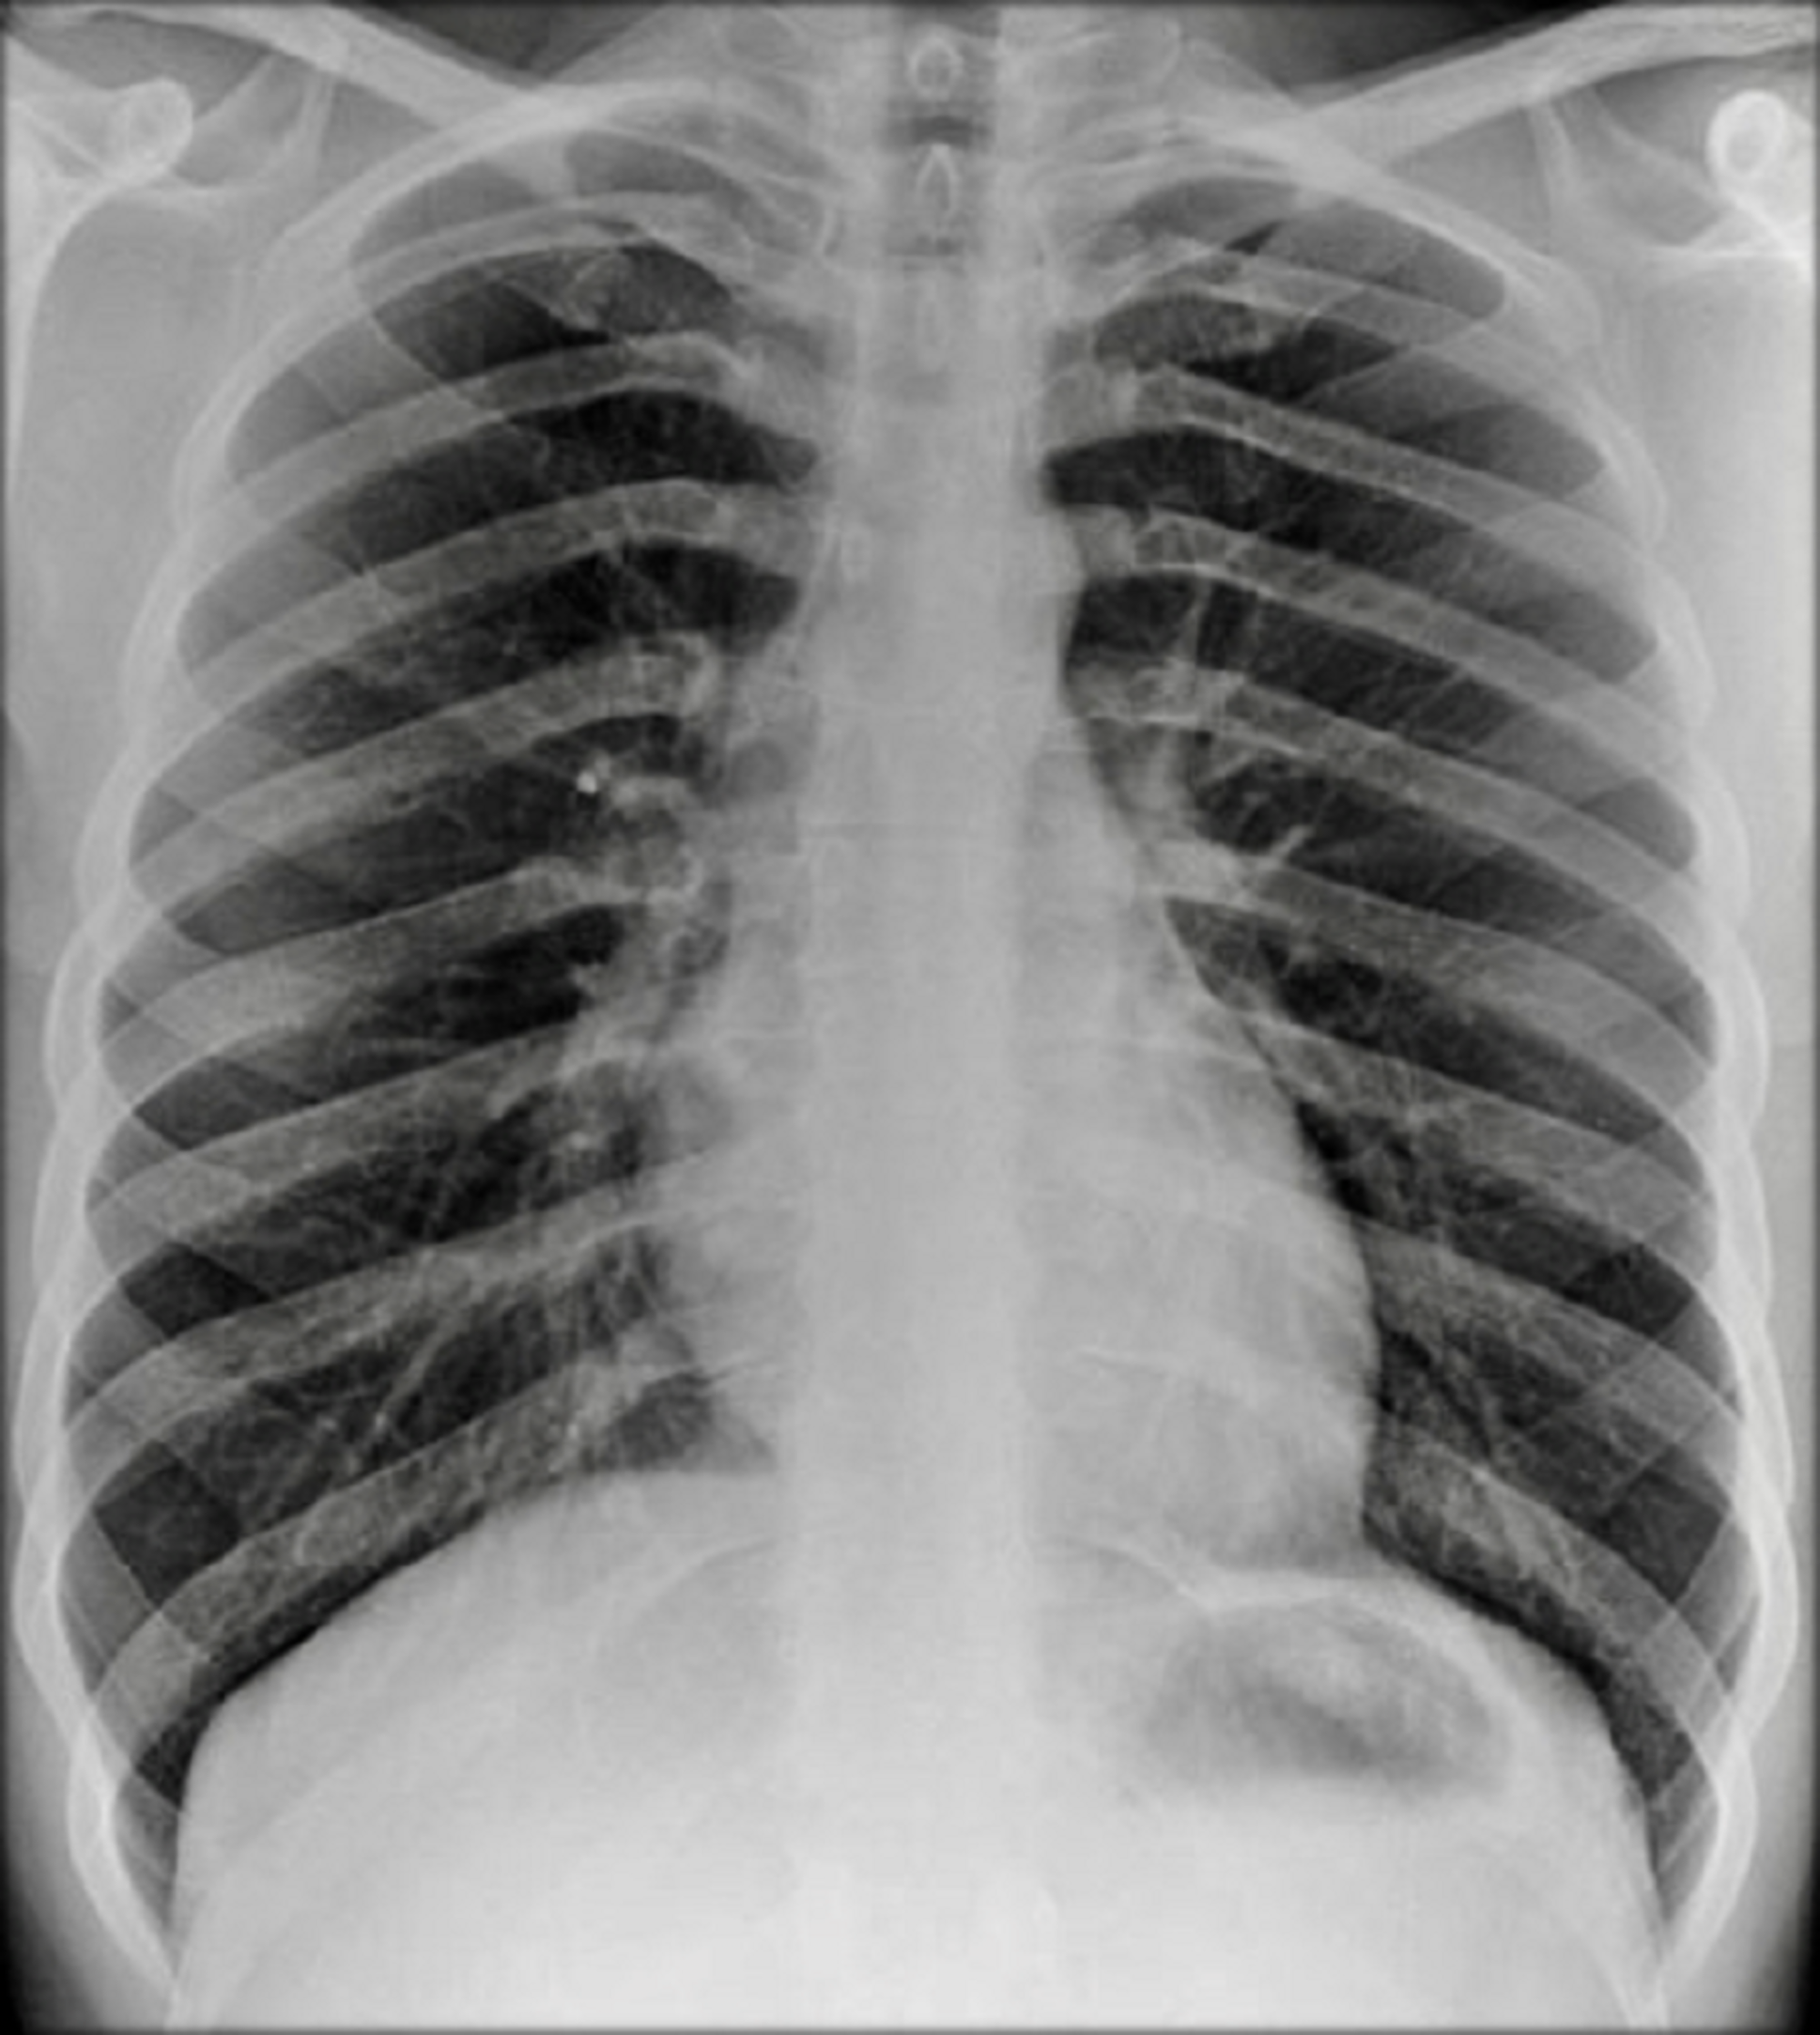

Cureus Pulmonary Involvement in Crohn’s Disease A Rare Case Report Crohn's Disease Chest X Ray Because they suppress parts of the immune system, all biologics carry an increased risk of. Biologic medicines are common treatments for people with crohn’s or colitis. The lesions are usually transmural,. Computed tomography enterography (cte) and magnetic resonance enterography (mre) have emerged as the most effective methods for imaging the small. Follow up us after tuberculostatic therapy showed complete resolution. Crohn's Disease Chest X Ray.

Crohn’s disease with severe lung involvement Archivos de Bronconeumología Crohn's Disease Chest X Ray Follow up us after tuberculostatic therapy showed complete resolution of the. The lesions are usually transmural,. Biologic medicines are common treatments for people with crohn’s or colitis. Because they suppress parts of the immune system, all biologics carry an increased risk of. Computed tomography enterography (cte) and magnetic resonance enterography (mre) have emerged as the most effective methods for imaging. Crohn's Disease Chest X Ray.

(PDF) AntiTNF Treatment and Miliary Tuberculosis in Crohn's Disease Crohn's Disease Chest X Ray Ibd, namely crohn disease and ulcerative colitis, has a variety of thoracic manifestations. The lesions are usually transmural,. Biologic medicines are common treatments for people with crohn’s or colitis. Computed tomography enterography (cte) and magnetic resonance enterography (mre) have emerged as the most effective methods for imaging the small. Because they suppress parts of the immune system, all biologics carry. Crohn's Disease Chest X Ray.